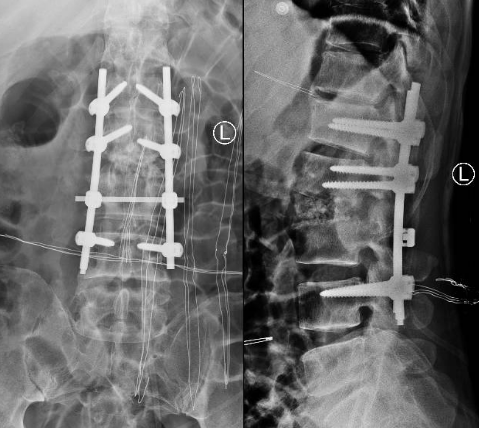

术前腰椎CT

术后X线片

患者出院后感腰部疼痛持续加重,到色漫网 门诊就诊,以“腰椎感染”收住入院。患者发病后腰椎CT及MRI均提示腰2-3椎间隙变窄,椎板破坏,综合以上资料诊断”腰椎结核”。入院后经口服四联抗结核药物治疗3周,患者自觉腰部疼痛减轻,午后无发热及盗汗后,在全麻下行颈后路病灶清除、椎间植骨、椎弓根钉棒系统内固定术。手术顺利,术后继续抗结核治疗。患者恢复顺利,术后1周下床活动,无特殊不适。术后2周拆线、出院,院外继续口服抗结核药物治疗,定期门诊复查。